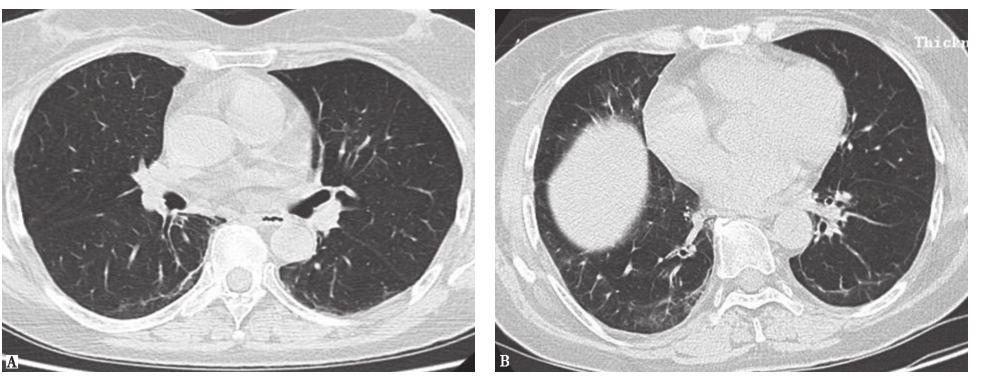

胸部HRCT:入院后复查胸部HRCT见双肺胸膜下磨玻璃影及斑片状实变影,双侧可见胸膜下线(图6)。

图6入院后胸部HRCT表现

图5放射性肺炎胸部影像学表现

男性患者,59岁,右下肺鳞癌放疗结束后6周(48Gy)出现双肺弥漫渗出。HRCT见右下叶癌性空洞,空洞周围实变(A),双肺磨玻璃样渗出(B)